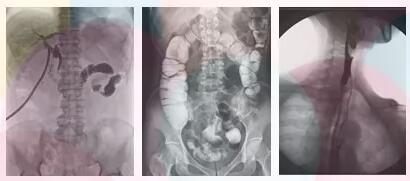

方面三、子宮輸卵管造影,優選動態平板dr

采集面積大,一次曝光即可顯示整個盆腔,大幅減少觀察時間,可控的瞬時照射避免受檢者吸收過多的X線,對育齡期婦女的檢查尤為重要。實時高清點片,可以在造影劑流動的過程中完成拍片,抓拍到關鍵圖像,清楚的了解管腔的具體通暢情況及堵塞部位,對檢查及診斷有非常重要的價值。